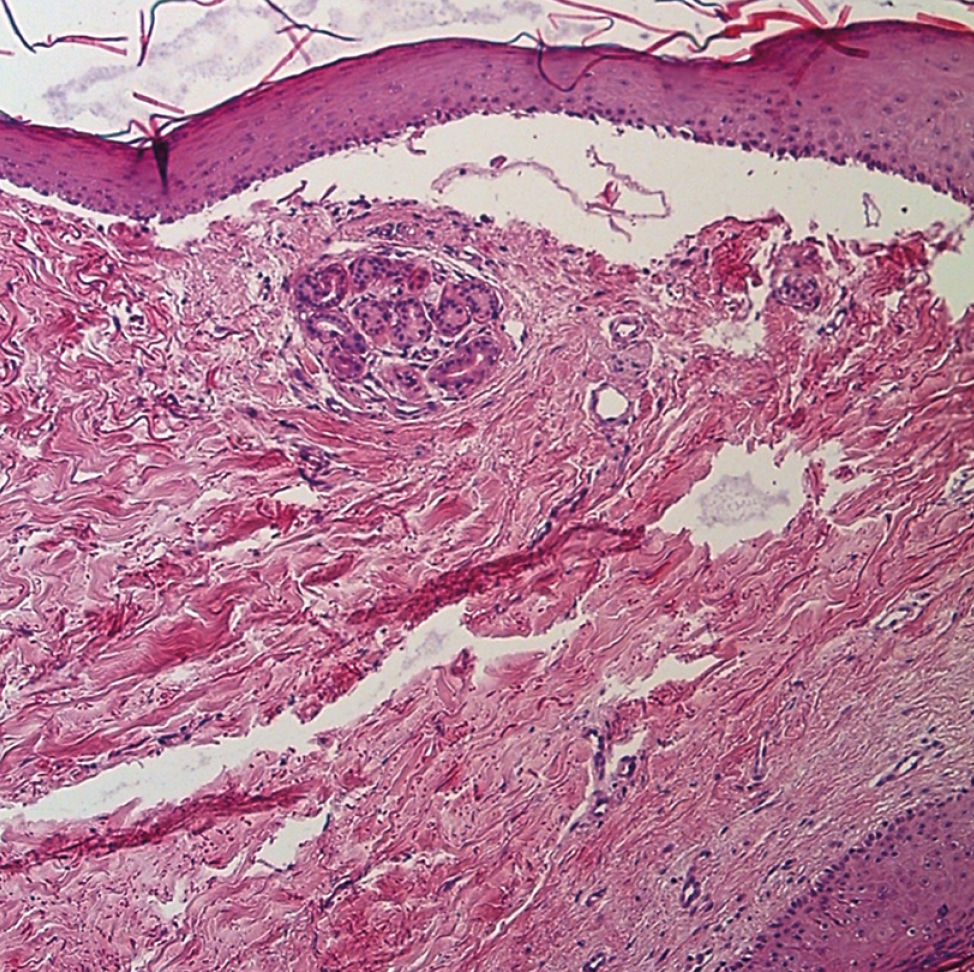

Histopathological examination: Histological examination of the skin flap biopsy revealed epidermal atrophy, focal vacuolization of basal keratinocytes, and edema of the papillary dermis, leading to the formation of subepidermal blisters. In the dermis, hyalinization and thickening of collagen bundles with subsequent sclerosis and dilation of lymphatic vessels were observed. Lymphoplasmacytic infiltrate was noted in the perivascular space and at the dermoepidermal junction (Fig. 7).

Conclusion: The morphological picture is consistent with the diagnosis of “localized scleroderma, bullous form.”

Fig. 7. Pathomorphological picture presents epidermal atrophy, focal vacuolisation of basal keratinocytes, swelling of the papillary layer of the dermis and subepidermal bullae.

The histological pattern of bullous scleroderma consists in thickening of collagen fiber bundles and hyalinization, dilation of the cutaneous lymphatic vessels, and the formation of subepidermal blisters at the level of the lamina densa. In the epidermis, atrophy is observed, with possible vacuolization of basal keratinocytes and infiltration of the dermoepidermal junction by lymphocytes and plasma cells [1, 25].